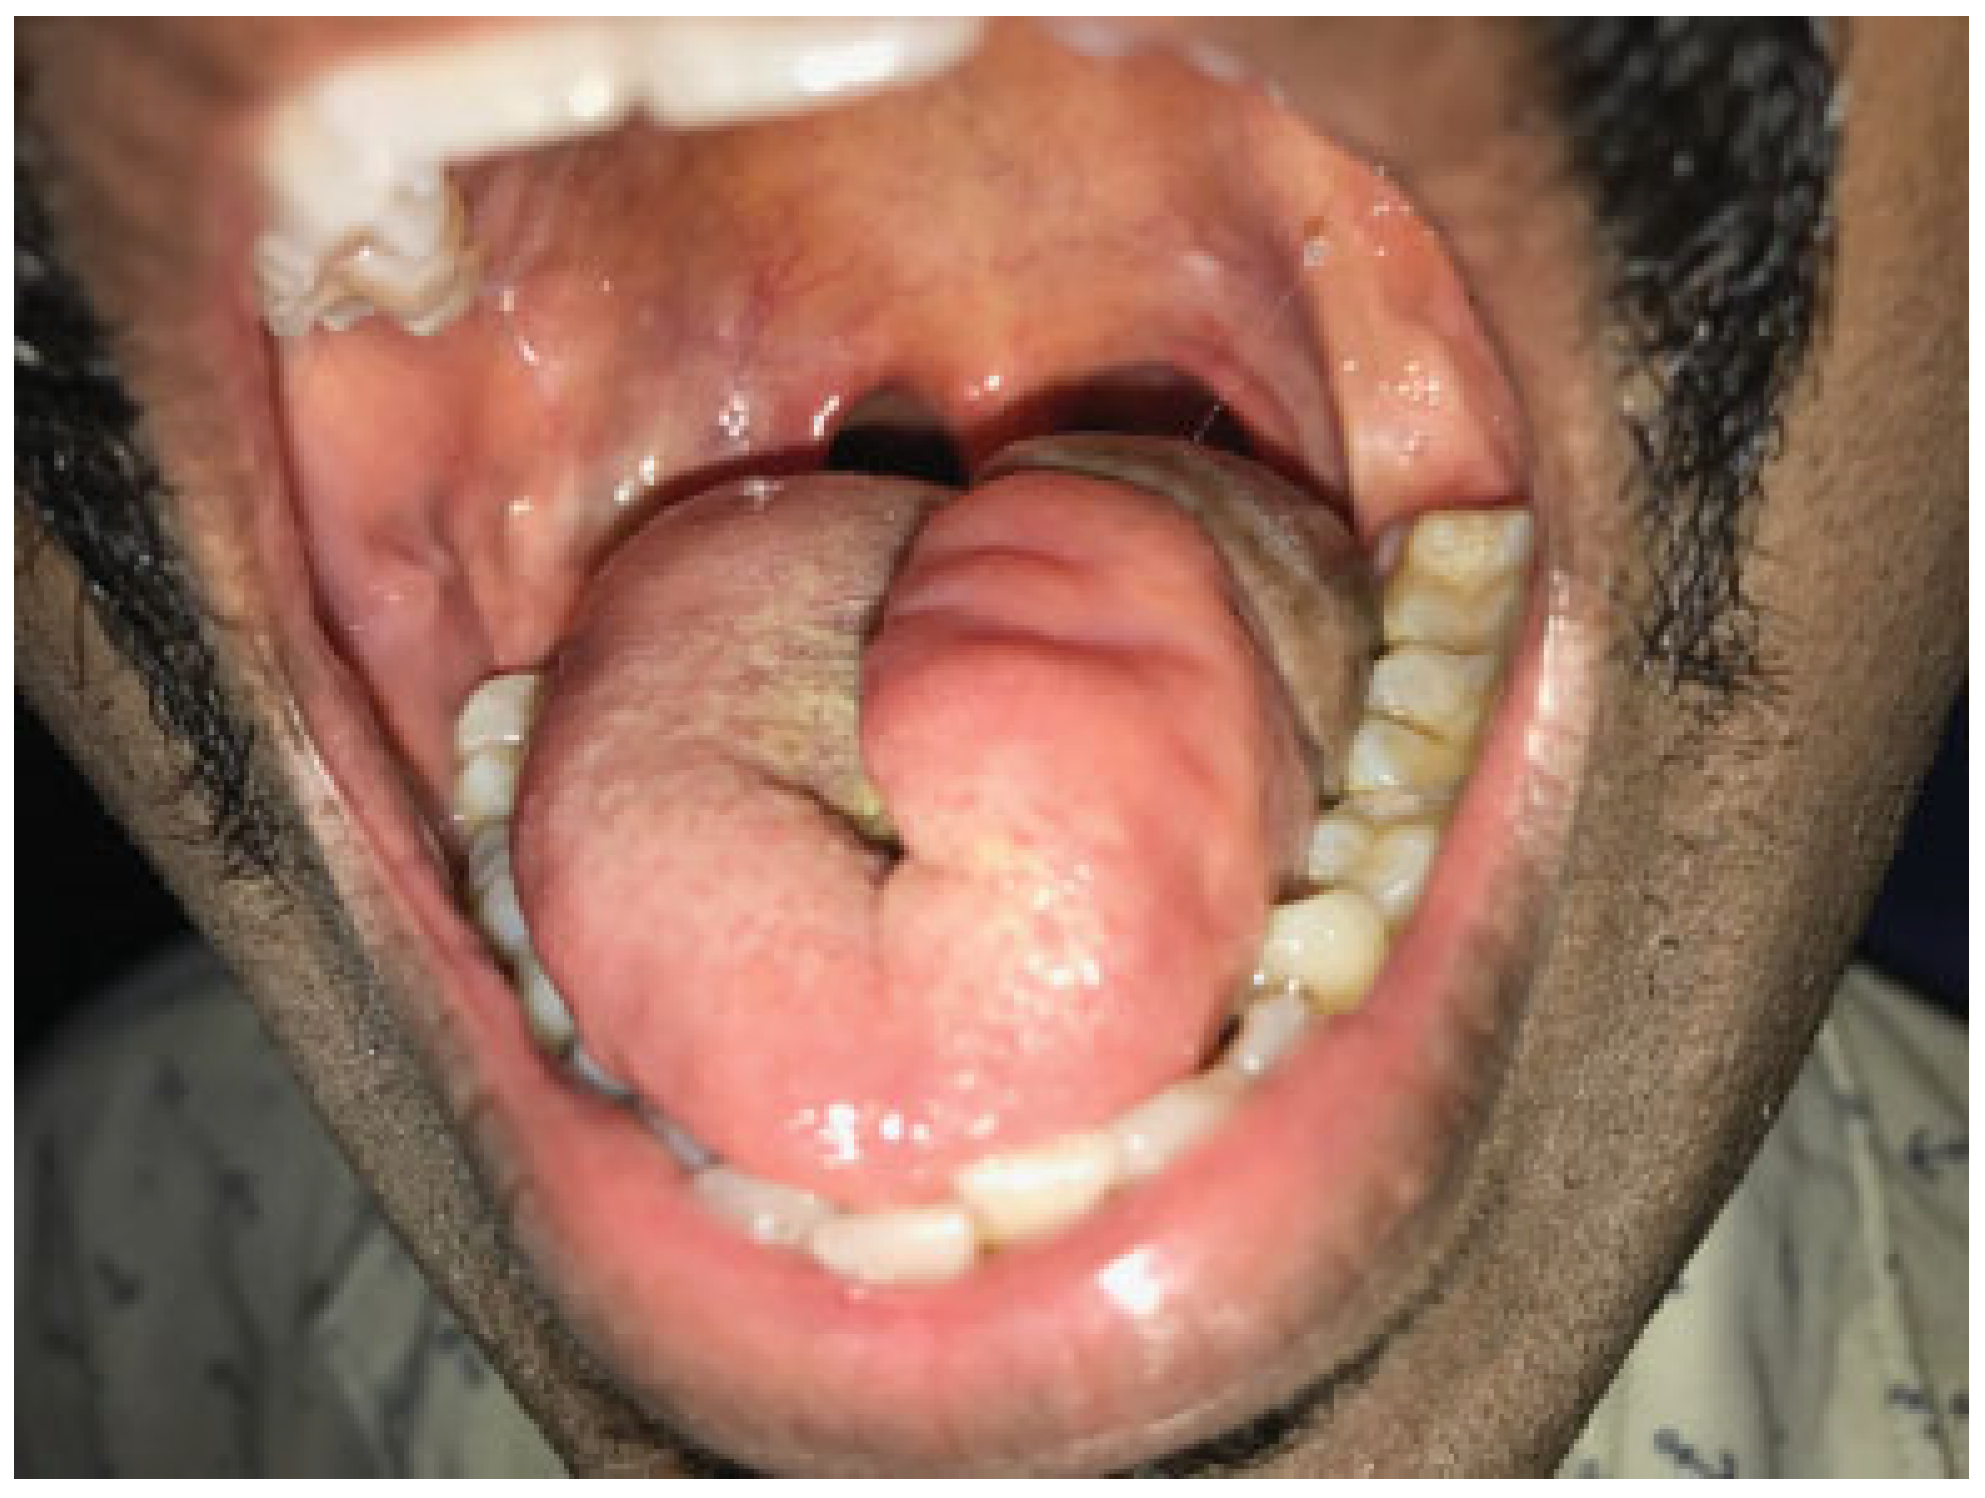

After endotracheal intubation, the patient underwent an elective tracheostomy. The procedure started with an ipsilateral selective neck dissection of levels I to III. Then the release of the suprahyoid musculature was done posteriorly, cutting the mylohyoid, hyoglossus, and posterior geniohyoid muscles. The carotid sheath and its contents were retracted laterally. Lingual and hypoglossal nerves were identified and preserved. The left lingual artery was ligated at its origin from the left external carotid artery. This technique of selective arterial ligation is performed to avoid postoperative hemorrhage from the bed of the tongue base resection. Attention was then diverted to the transoral robot-assisted part of the surgery. The mouth opening was stabilized with Boyle Davis mouth gag and tongue blade with Draffin bipod after insertion of a cheek retractor. A tongue stitch with silk was performed to keep the tongue protruded. Robotic docking into the mouth was done, with the robotic arms along with the 30-degree camera. A wide area around the tumor with a margin of 1 cm was mapped (Figure 2). The excision of the tumor was performed with robotic instruments, monopolar cautery spatula, and Maryland bipolar forceps. da Vinci Xi robot (Intuitive Surgical Inc., Sunnyvale, CA) was used. An upward facing camera, 8 mm, 30 degrees, was used for visualization. The excision crossed the midline, and the robotic cuts were connected to those made from the neck, resulting in a defect connected to the neck.

Figure 2. Transoral mapping of the tongue prior to resection.